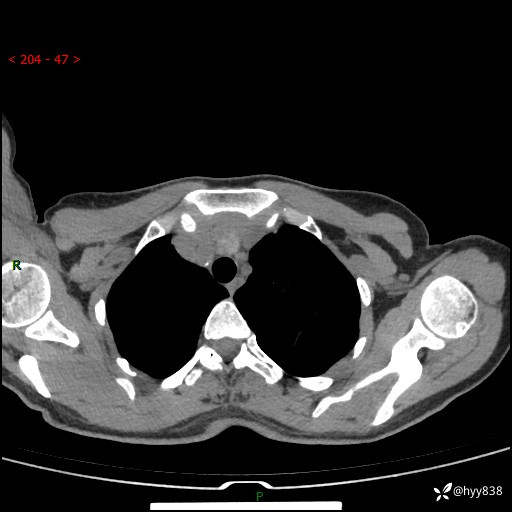

胸部CT平扫